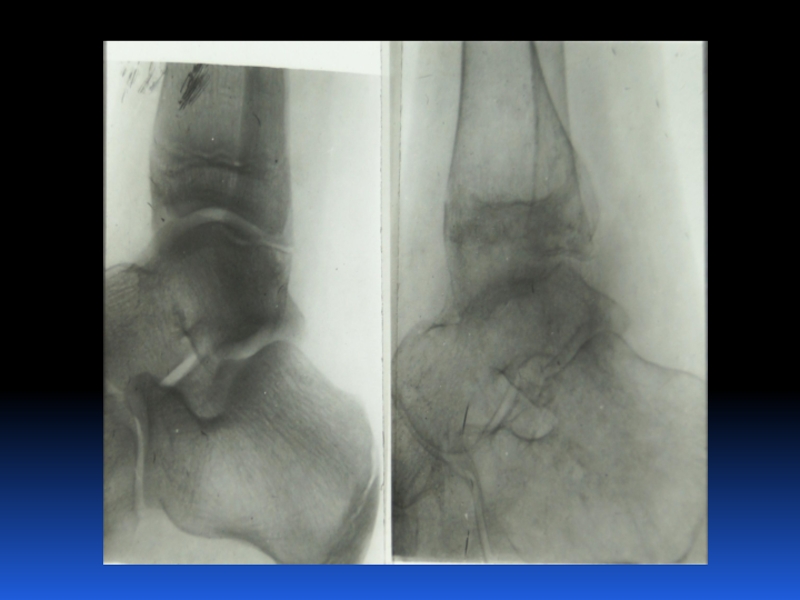

Остеопороз – это системное заболевание скелета, характеризующееся снижением костной массы и нарушением микроархитектоники костной ткани, с последующим увеличением хрупкости костей, со склонностью к патологическим переломам.

Слайд 2 Остеопороз – это системное заболевание скелета, характеризующееся снижением костной

массы и нарушением микроархитектоники костной ткани, с последующим увеличением хрупкости

костей, со склонностью к патологическим переломам.